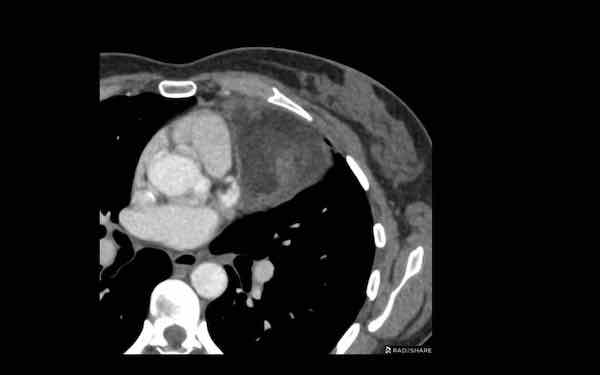

Các hình ảnh này của một bệnh nhân nam 68 tuổi, vừa trải qua phẫu thuật bắc cầu động mạch vành.

Bệnh nhân than phiền khó thở.

Nồng độ D-dimer cao và CT được thực hiện để tìm kiếm thuyên tắc phổi.

Hình ảnh

Có một khối trong trung thất trước mạch máu.

Tỷ trọng là 44